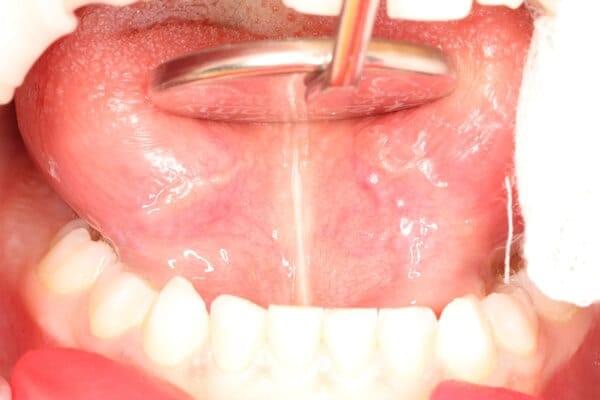

Дівчинка 2 років, але зуби вже мають глибокі ураження із залученням у запальний процес пульпи (“нерва”) зуба. На жаль, так трапляється і зволікати в такому випадку не можна. Було проведено лікування в умовах анестезіологічного забезпечення під контролем досвідченої анестезіологічної команди. Передні зубчики відновлено естетичними коронками, на жувальних зубчиках проведена герметизація фісур, а один вже має глибоке ураження карієсом, тому теж покритий коронкою. Одразу після лікування ясна можуть виглядати дещо травмованими, але за кілька днів вони повністю відновляться.